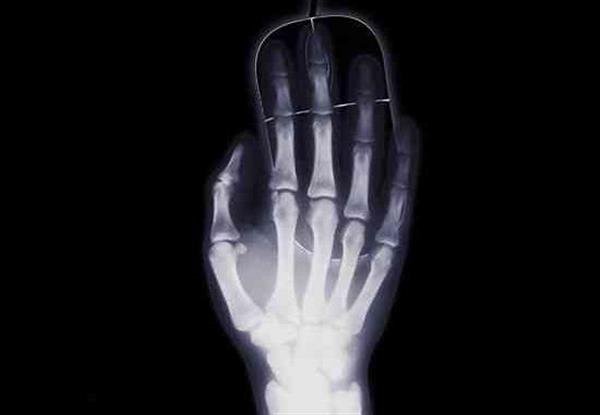

值得注意的是,这种3D打印骨头的新方法还将使用一种叫做聚羟基丁酸酯(PHB)的可充分生物降解材料。西伯利亚联邦大学(SFU)生物科学博士Catherine Shishatskiy解释说,3D打印技术让他们在设计和制作骨骼方面获得了巨大的自由。此外,由于断层照影技术,比如CT和核磁共振等,的使用,其3D模型的精度可以达到前所未有的水平。不可否认,扫描和3D打印技术的组合为自定义设计解剖植入物,比如3D打印骨骼,打开了大门。

参与该项目的另一位研究人员Constantine Kisterskiy还指出,通过将这种可生物兼容的材料用于骨骼的增材制造,即将该材料有效地一层层融合在一起,他们还消除了对一定化学结构和胶粘剂的需求。据e键打印了解,这种3D打印材料是俄罗斯Krasnoyarsk地区的科学家在以前的研究项目基础上开发出来的。根据俄罗斯媒体的报道,SFU的一位医学博士Ekaterina Shishatskaya曾经因为此类材料的研究在2010年获奖。